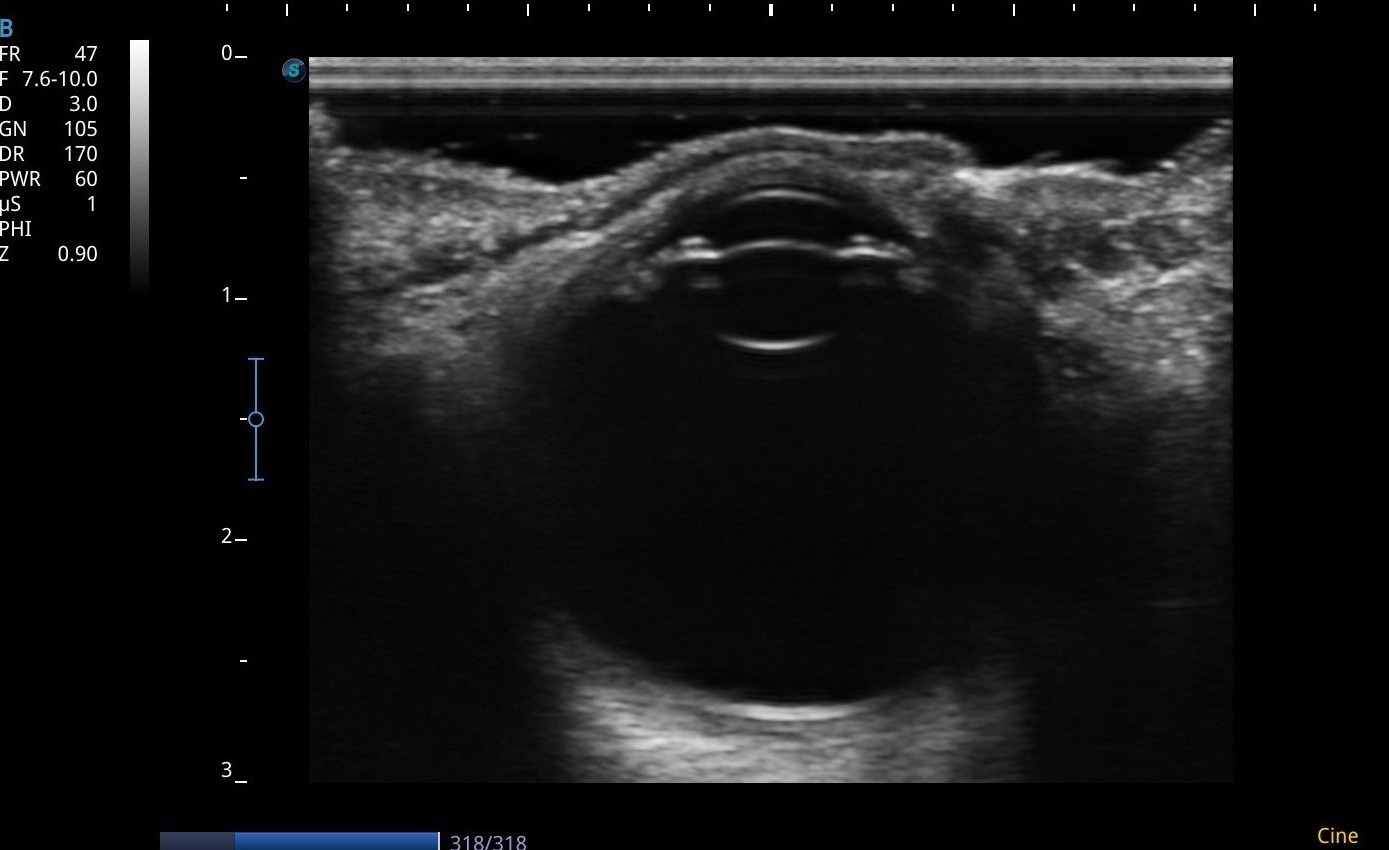

En la segunda parte de la sesión se utilizó un ecógrafo para la puesta en práctica de lo expuesto a nivel teórico y se obtuvieron imágenes de los asistentes. Para el estudio anatómico, el empleo de una sonda lineal permite la visualización de las diferentes estructuras mediante un recorrido axial y longitudinal, además de la medición del globo ocular y el nervio óptico. Dentro del estudio dinámico, la sonda sectorial ayuda a conocer el estado de la cámara y humor vítreos, y el flujo de la arteria y vena oftálmicas.

El ojo es un órgano superficial y radiosensible que se puede beneficiar del uso de los ultrasonidos para su estudio anatómico y dinámico.

Es necesario disminuir la potencia acústica para evitar iatrogenia.